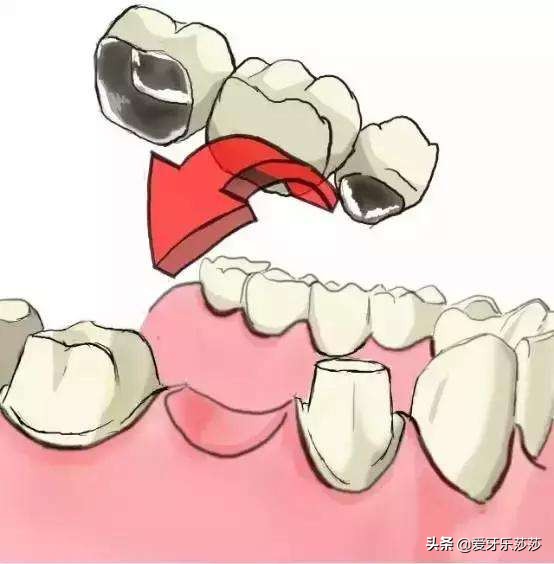

最后呢,是烤瓷冠的类型~

一般我们做的烤瓷冠大都分为单冠和连冠,连冠的烤瓷冠是无法单颗移动,会直接影响矫正效果。因此当小伙伴戴的是搭桥连冠烤瓷冠的话,则需要考虑拆除,等矫正牙齿后完成后再重新制作。若连冠烤瓷牙涉及到的位置是无需移动呢!,小伙伴则可以选择隐形矫正来移动其他牙齿。